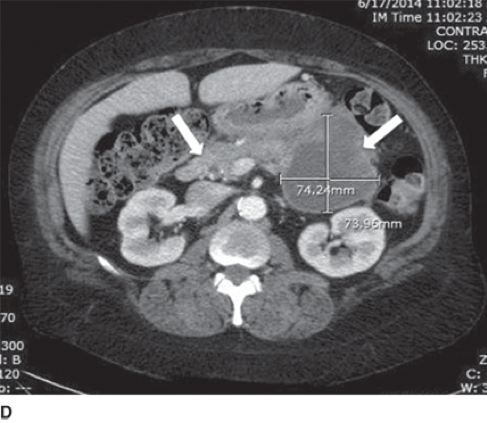

solid pseudopapillary neoplasm

A

o Low grade malignant neoplasm, 15% get mets

o Women in 20s

o Sx: intra-abdominal mass, palpable on exam

o Activating Mutation in beta-catenin

o cystic areas filled w/ hemorrhagic debris,

o Histo: cells as solid sheets, pseudopapillary,